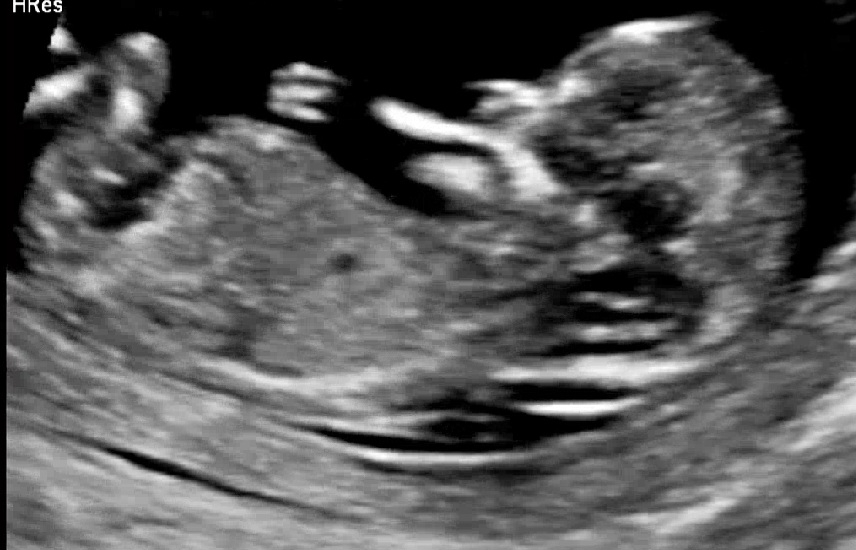

12주4일 각도법 성별 보이시는분 있으신가요?❤️

여아든 남아든 저는 상관없는데 궁금하긴하네요ㅎㅎ 성별 보이시는분?♡ 그리구.. 저 입에 있는건 뭘까용?